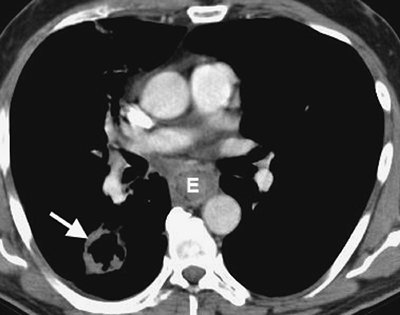

FIGURE 6-21. Hodgkin lymphoma. A: CT scan of a 59-year-old man with shortness of breath shows a homogeneous mass of soft tissue attenuation (M) compressing the left atrium (LA), nearly encasing the aorta (A), and abutting the esophagus (dashed arrow) and azygous vein (solid arrow). There is also a right pleural effusion (E). B: CT scan at a more inferior level shows retrocrural lymphadenopathy (A).